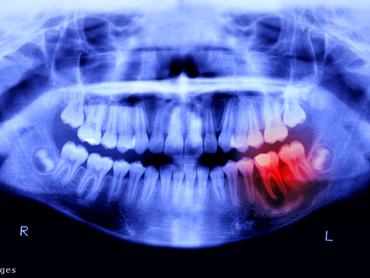

Az Európai Unióban teljes körű tilalmat vezettek be a fogászati amalgám használatára. Ez annak az intézkedéscsomagnak a része, amelynek értelmében uniós tilalom alá esik minden higanyt tartalmazó termék gyártása, behozatala és kivitele.

Az Európai Unió Tanácsa által elfogadott rendelet értelmében 2025. január 1-jétől mindenki számára tilos lesz a fogászati amalgám használata. Eddig a szabályozás csak a 15 év alatti gyermekekre, állapotos és szoptató nőkre vonatkozott, de az új rendelkezések kiterjesztik a tilalmat mindenki másra is – adták hírül a testület honlapján.

A fogászati amalgám kivitele 2025. január 1-jétől válik tilossá, míg az EU-ban történő gyártás és behozatal 2026. július 1-jével szűnik meg. A fogorvosoknak mindazonáltal lehetőségük lesz kivételt tenni, amennyiben úgy ítélik meg, hogy páciensük esetében a fogászati amalgám használata elengedhetetlen. Persze, hogy az ehhez való anyagot honnan szerzik majd be, ha gyártási és behozatali tilalom alá esik, az még a jövő zenéje. Annyit lehet most tudni, hogy az Európai Unió Bizottsága 2029. december 31-ig felülvizsgálja majd a fogászati amalgám használatára vonatkozó kivételeket, figyelembe véve a higanymentes alternatívák elérhetőségét.